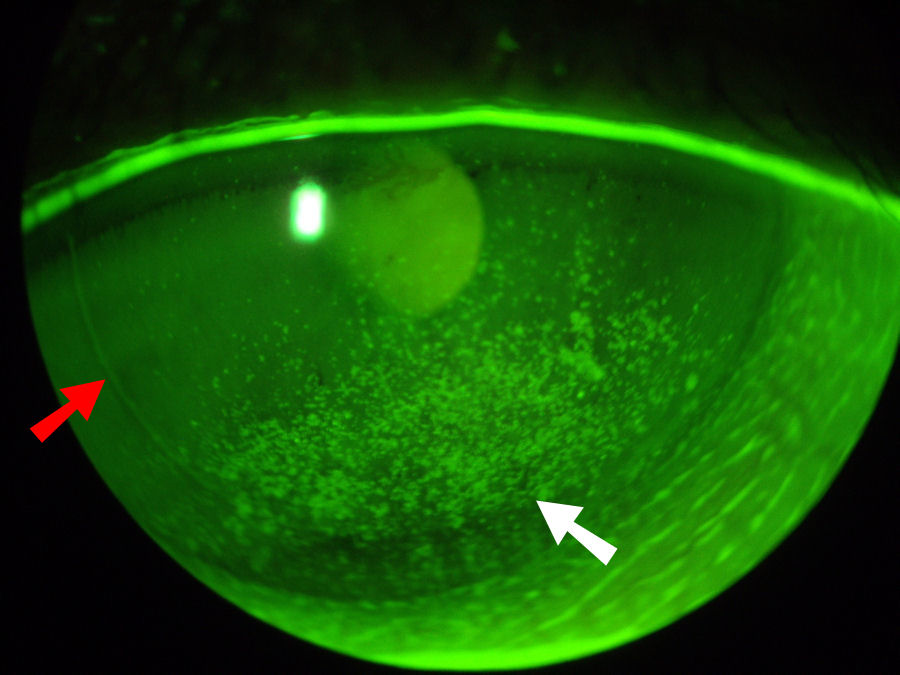

КК был введен для лечения дальнозоркости. КК использует иглоподобный зонд для доставки радиочастотной энергии (тепла) к коллагену периферической части роговицы в кольце индивидуально расположенных точек. Нагревание приводит к сокращению коллагена роговицы, что приводит к утолщению центральной части роговицы. Ниже вы можете четко видеть восемь точек, расположенных кольцом вокруг роговицы, в которые были введены зонды для КФК. Красная стрелка указывает на одно из мест КФК. Сразу за кольцом СК-пятен находится край лоскута LASIK, обозначенный белой стрелкой. Такие повреждения роговицы никогда полностью не заживают.